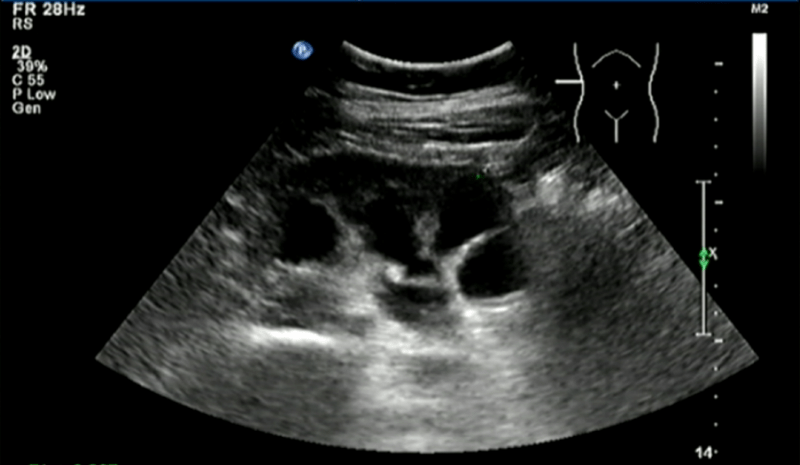

手术前B超提示右肾重度积液 。

今年7月 , 她来到广州医科大学附属第一医院复查时发现右肾重度积液 , 肾积水范围8.8cm*4cm , 肾脏被挤压变薄 , 右肾的功能也下降至正常的1/5 , 如果进一步发展 , 右肾长期受压会导致肾脏功能不可逆的损伤 。